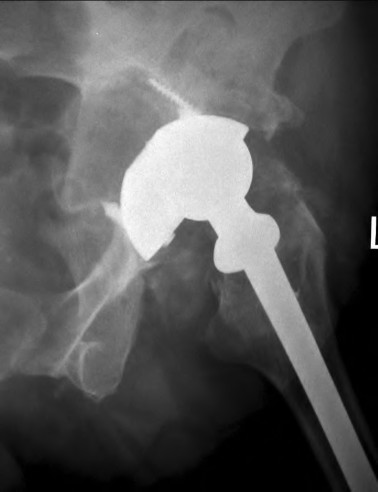

A 68-year-old female is scheduled for a total hip arthroplasty. Preoperative standing and sitting lateral spine-pelvis radiographs demonstrate a change in sacral slope of less than 10 degrees from standing to sitting. Which of the following component positioning strategies is most appropriate given this finding?

During a revision total hip arthroplasty, you encounter severe acetabular bone loss. Preoperative radiographs demonstrate up and in migration of the cup past Kohler's line, superior migration of 4 cm, and intraoperatively you note destruction of >60% of the acetabular rim, with independent movement of the superior and inferior hemipelvis. What is the most appropriate reconstructive option?

A 45-year-old female with developmental dysplasia of the hip (DDH) presents for THA. Preoperative radiographs show the femoral head is subluxated, with 80% proximal migration relative to the height of the normal true acetabulum. Based on the Crowe classification, what type of dysplasia does she have?

According to the classic work by Lewinnek, what is the "safe zone" for the orientation of the acetabular component in total hip arthroplasty to minimize the risk of postoperative dislocation?

A 68-year-old patient with a fused lumbar spine from L2 to the pelvis (pelvic incidence minus lumbar lordosis mismatch) is scheduled for a THA. How does this spinopelvic stiffness affect the optimal acetabular cup positioning to minimize the risk of dislocation?

Radiographs of a failed THA demonstrate severe periprosthetic osteolysis. The acetabular component has migrated 4 cm superiorly and 2 cm medially past Kohler's line, and the radiographic teardrop is completely destroyed. Which Paprosky acetabular defect is present?